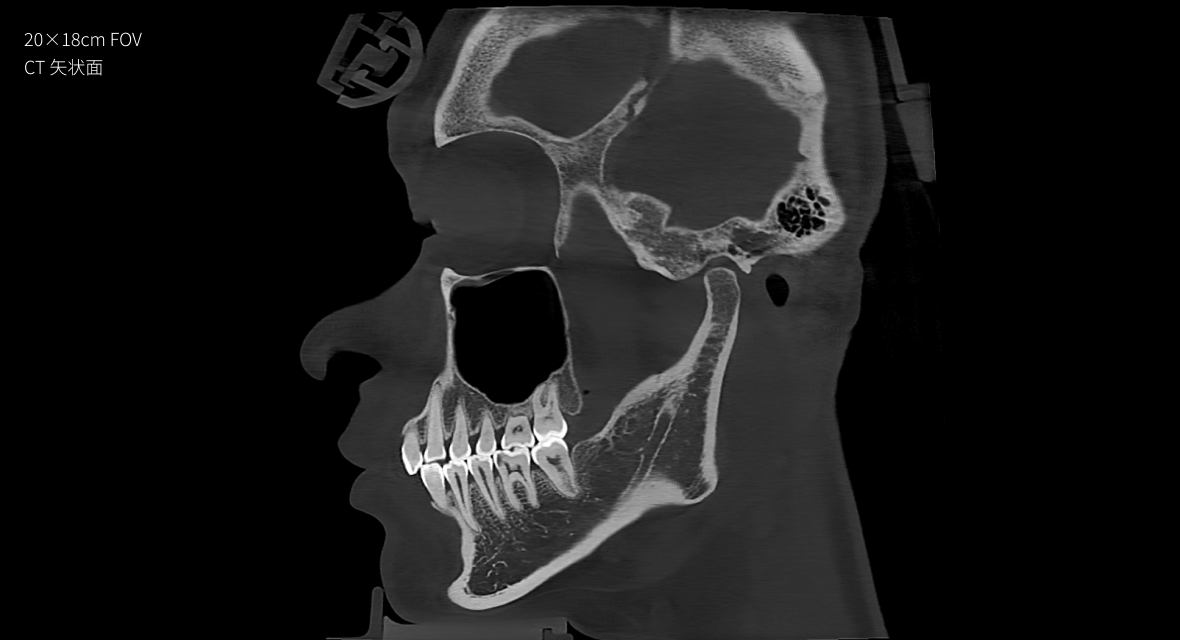

高清超大视野

• 20×18cm

最大视野

颌面全况,一览无余。基于双射源成像技术和核心影像算法,在实现大视野成像的同时,影像清晰度也能兼顾。

20×18cm

非拼接大视野